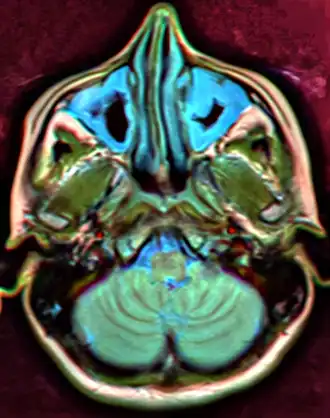

MRI image showing sinusitis. Edema and mucosal thickening appear in both maxillary sinuses.